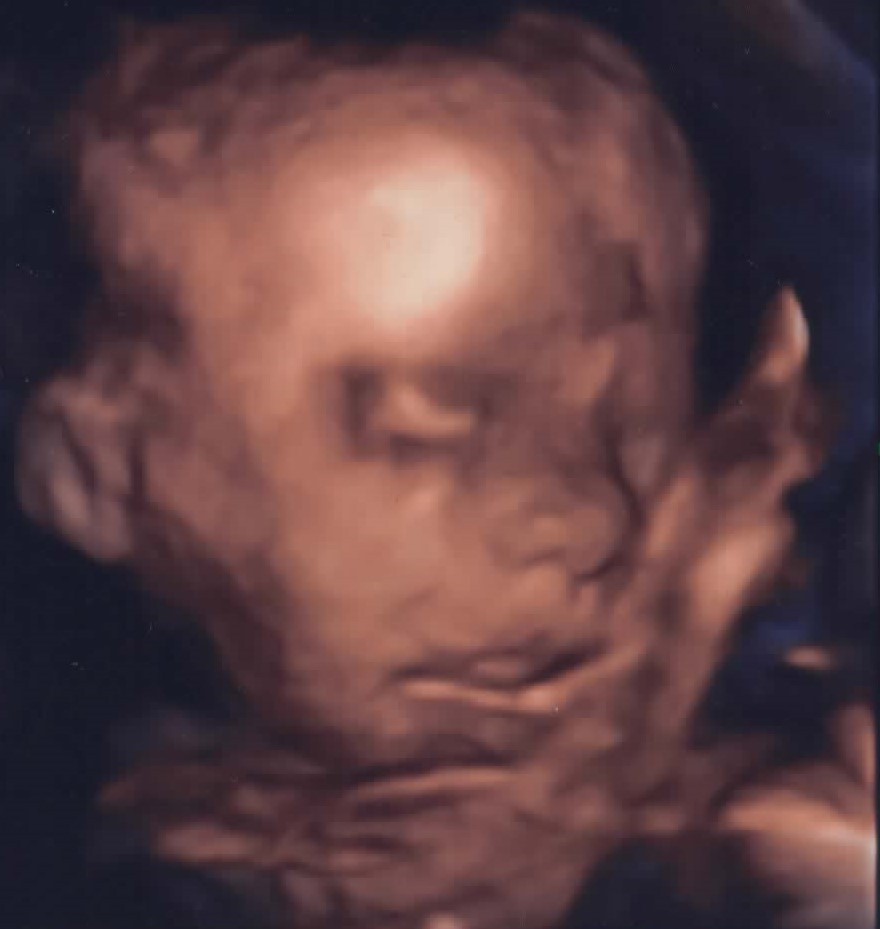

Ignaś przyjdzie na świat z wrodzoną wadą serca pod postacią zespołu niedorozwoju serca prawego, przełożenia wielkich pni tętniczych i przerwanego łuku aorty. Jego mama 26 września ma zostać przyjęta do Kliniki Uniwersyteckiej, w Munster, w Niemczech, a obecnie prosi o pomoc w ratowaniu życia nienarodzonego syna.

Wadę serca wykryto w 24. tygodniu ciąży. W najlepszym wypadku maleństwo czekają 3 operacje na otwartym sercu, a pierwsza ratująca życie musi się odbyć zaraz po porodzie, dlatego też poród musi się odbyć w miejscu, w którym zostanie przeprowadzona operacja.